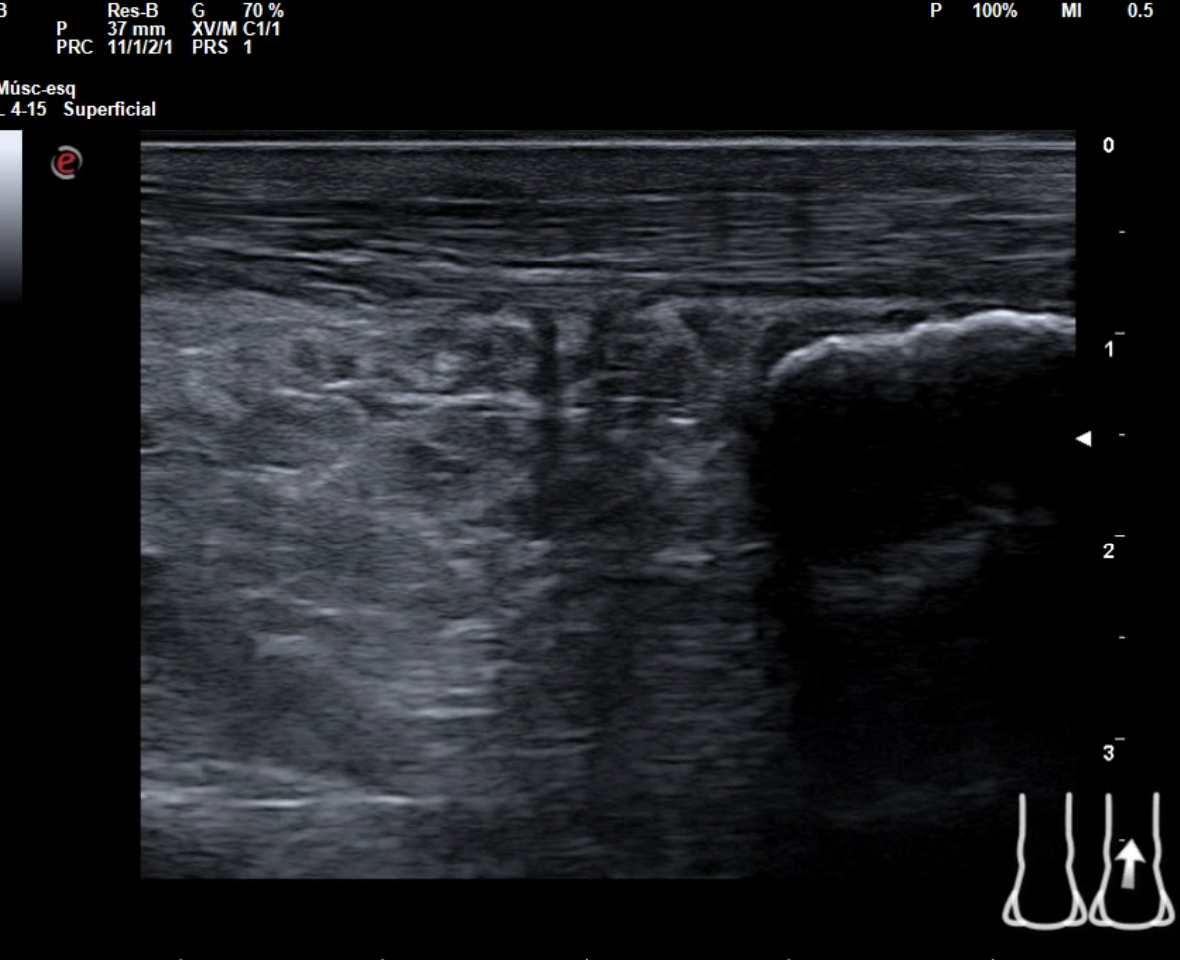

Hallazgos ecográficos

En tendón aquíleo izquierdo se aprecia rotura completa con solución de continuidad de 2 cm localizada a 5,7 cm de su inserción en el calcáneo. Presenta áreas hipoecoicas peritendón que sugieren hematoma secundario. En el aquíleo derecho presenta leve hipoecogenicidad y engrosamiento del tendón sin solución de continuidad que sugiere tendinosis. Importante componente inflamatorio. No datos de TVP. Poplítea y safena externa permeables y compresibles en ambas extremiedades.

Juicio clínico: Rotura completa de tendón de Aquiles izquierdo. Tendinosis aquílea derecha.